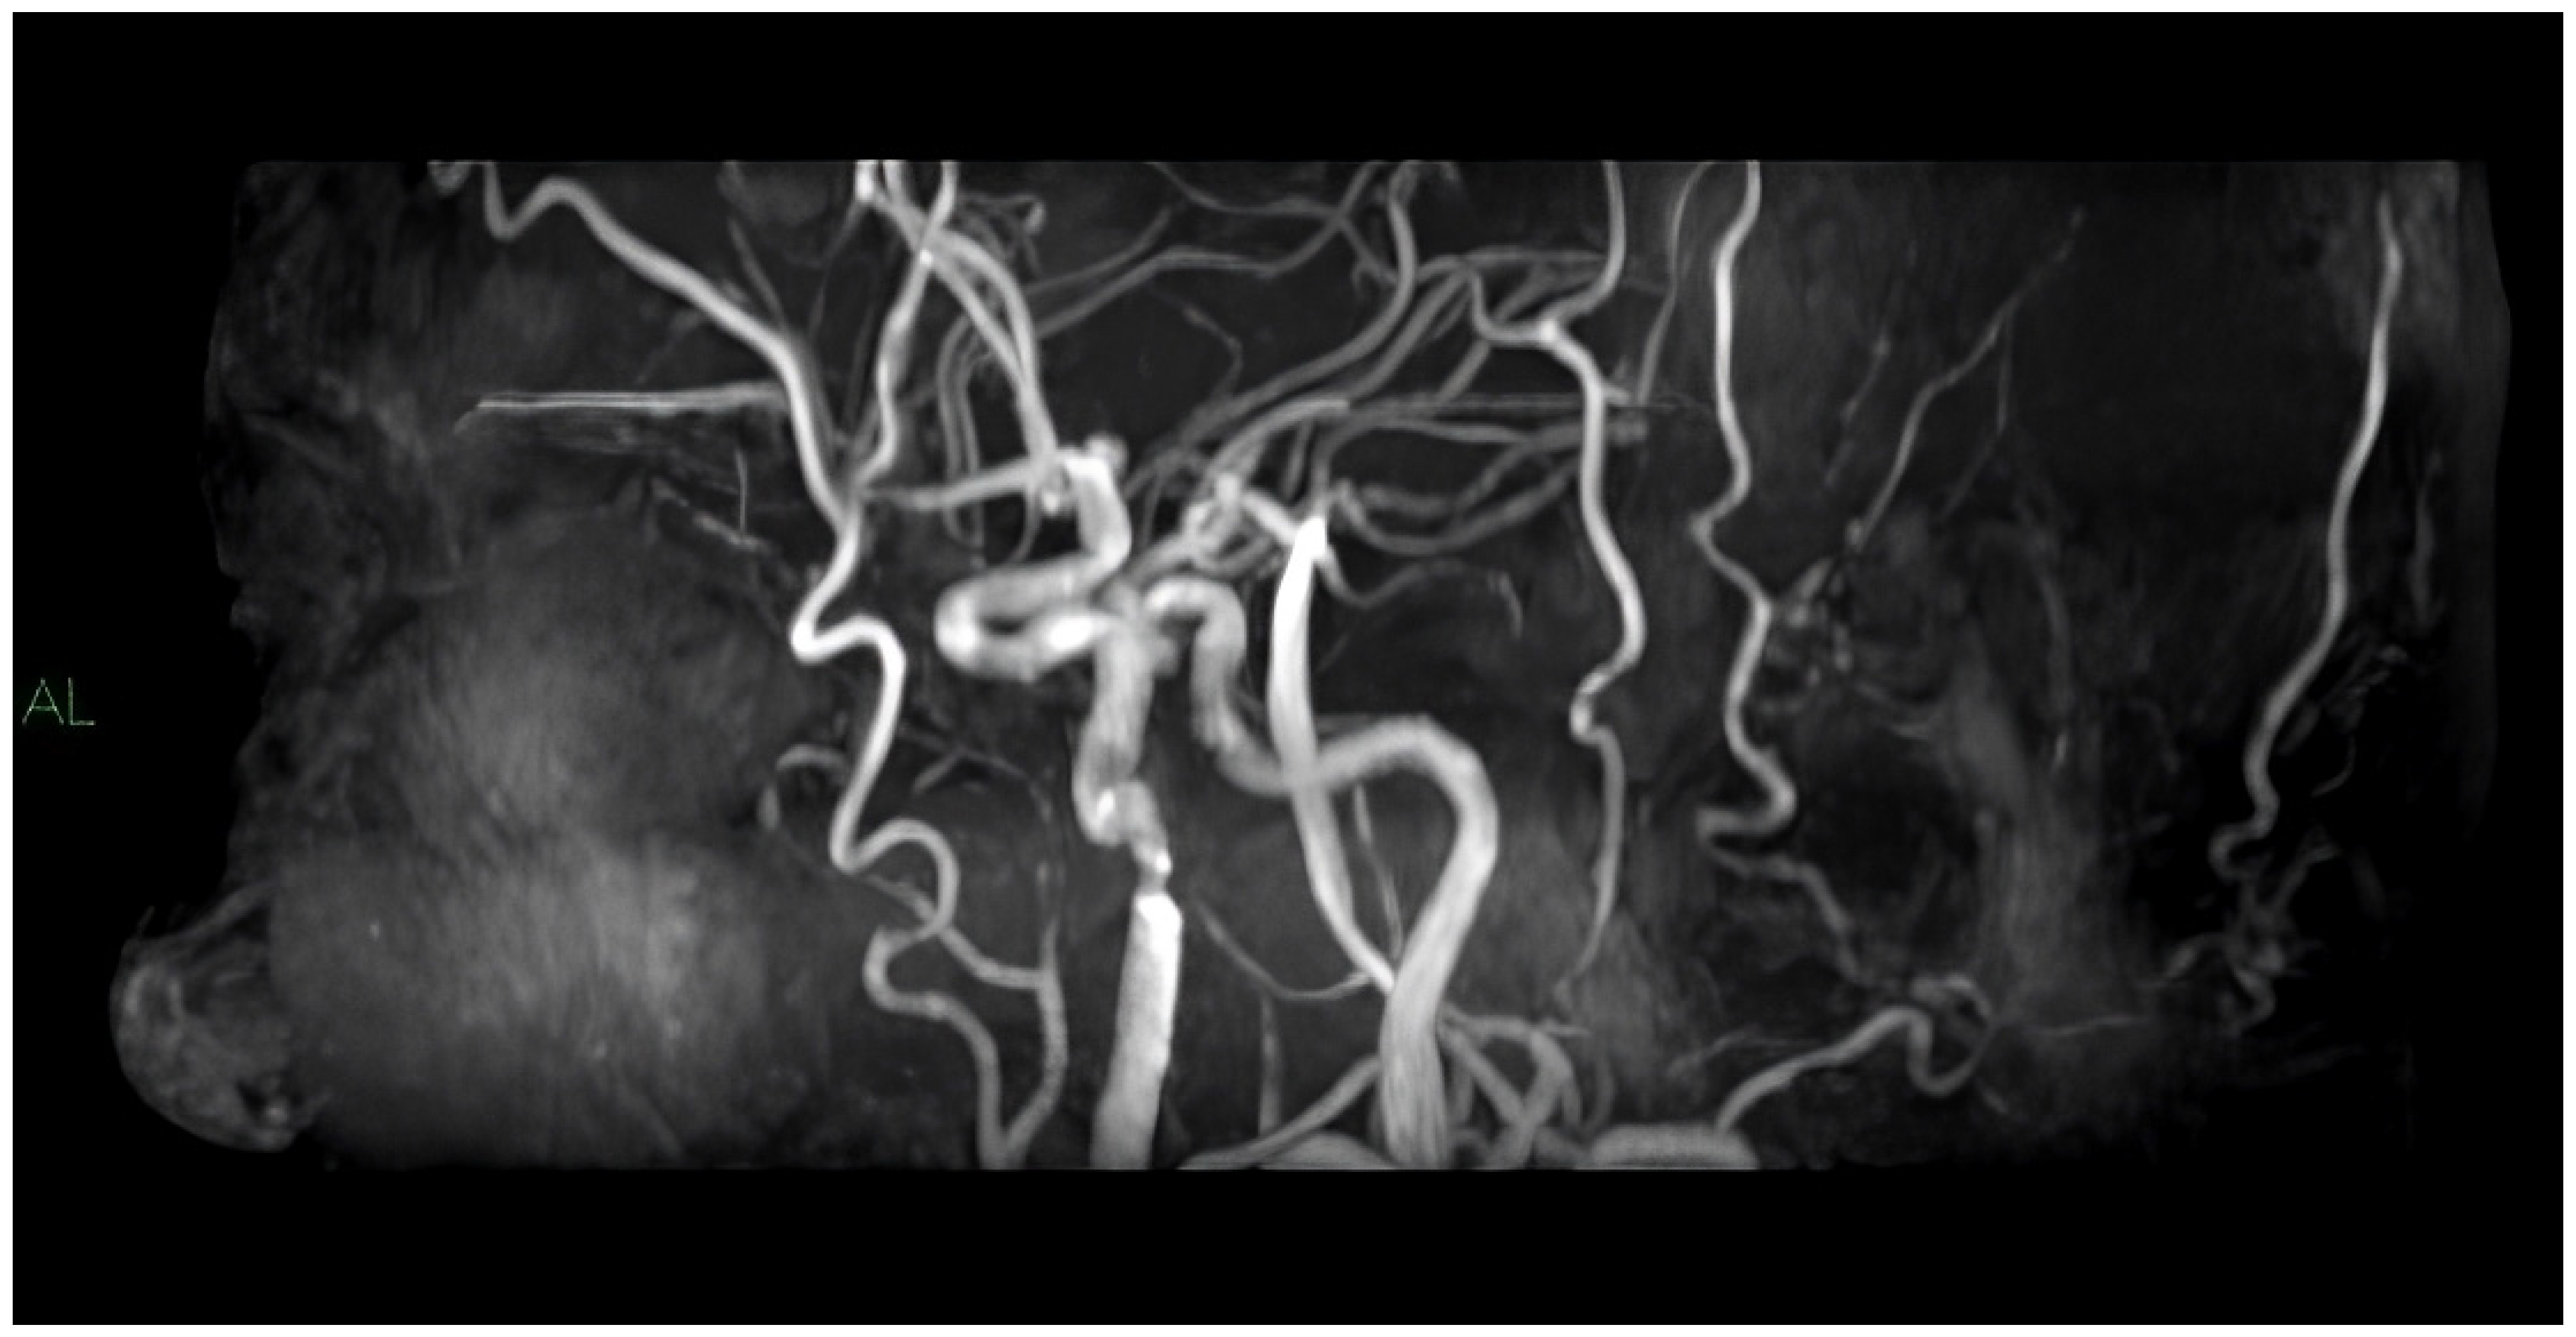

4. MRI